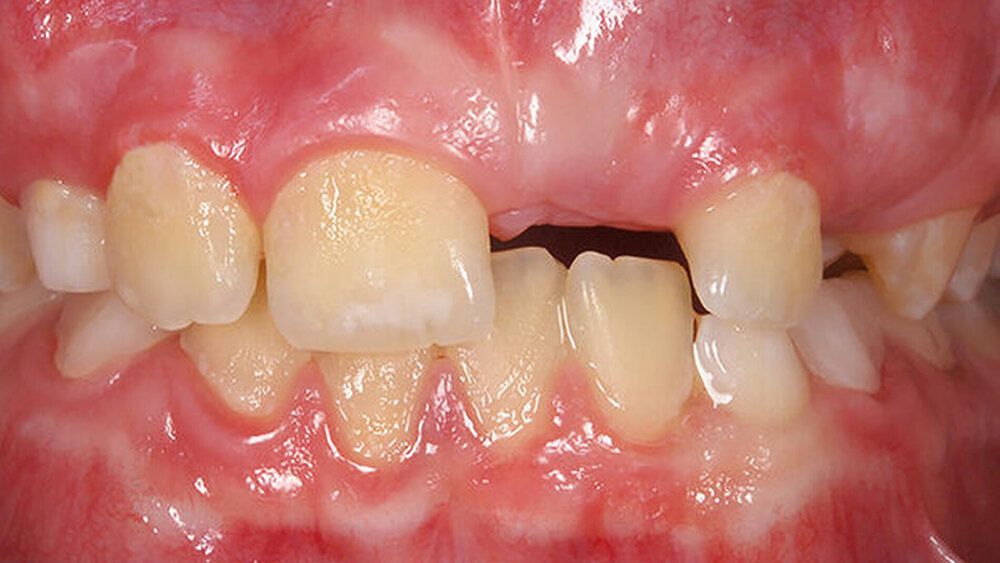

Neben der Beurteilung der Platzverhältnisse sollte auch die Okklusion in allen drei Dimensionen (vertikal, transversal und sagittal) überprüft werden, denn bereits in dieser frühen Phase können Dyskinesien und statische Funktionsstörungen die Entwicklung nachhaltig stören [Grabowski, 2007]. Ungünstige Umwelteinflüsse und Milieufaktoren spielen bei vielen kieferorthopädischen Anomalien eine wichtige Rolle, wobei es oft schwierig ist, den Anteil von umweltbedingten Faktoren/Milieufaktoren und genetischer Disposition exakt zu bestimmen. Allerdings wird der offenen Mundhaltung, die mit einem inkompetenten Lippenschluss und kaudaler Zungenruhelage vergesellschaftet ist, ein besonders nachteiliger Einfluss auf die physiologische Entwicklung zugeschrieben. Besonders häufig werden bei diesen statischen Haltungsschwächen das Auftreten eines transversal unterentwickelten Oberkiefers, ein vergrößerter oder reduzierter Overjet sowie ein offener Biss beobachtet [Grabowski, 2008]. Insbesondere beim offenen Biss wirkt sich zudem eine gewohnheitsmäßige oder anatomisch bedingte Mundatmung nachteilig auf die vertikale Entwicklung des Gesichts aus [Linder-Aronson, 1983]. Bei Verdacht auf eine anatomisch bedingte Mundatmung sollte zusätzlich HNO-ärztlich überprüft werden, ob organische Blockaden beseitigt werden können. Persistierende Lutschgewohnheiten können ebenfalls einen ungünstigen Einfluss auf den orofazialen Reifungsprozess nehmen [Dausch-Neumann, 1983]. Neben einer vergrößerten Frontzahnstufe (Abbildung 2) oder einem anterior offenen Biss als direkte Lutschfolgen erfolgt zudem meist keine Umstellung auf ein somatisches Schluckmuster, wobei diese sekundären Lutschfolgen später nur schwer und nur mit hohem Aufwand therapiert werden können [Cozza, 2005]. Auch hierbei kann zum Beispiel das Eingliedern einer Mundvorhofplatte (MVP) als interzeptive Maßnahme das Abgewöhnen von Gebiss schädigenden Gewohnheiten unterstützen [Dausch-Neumann, 1983].